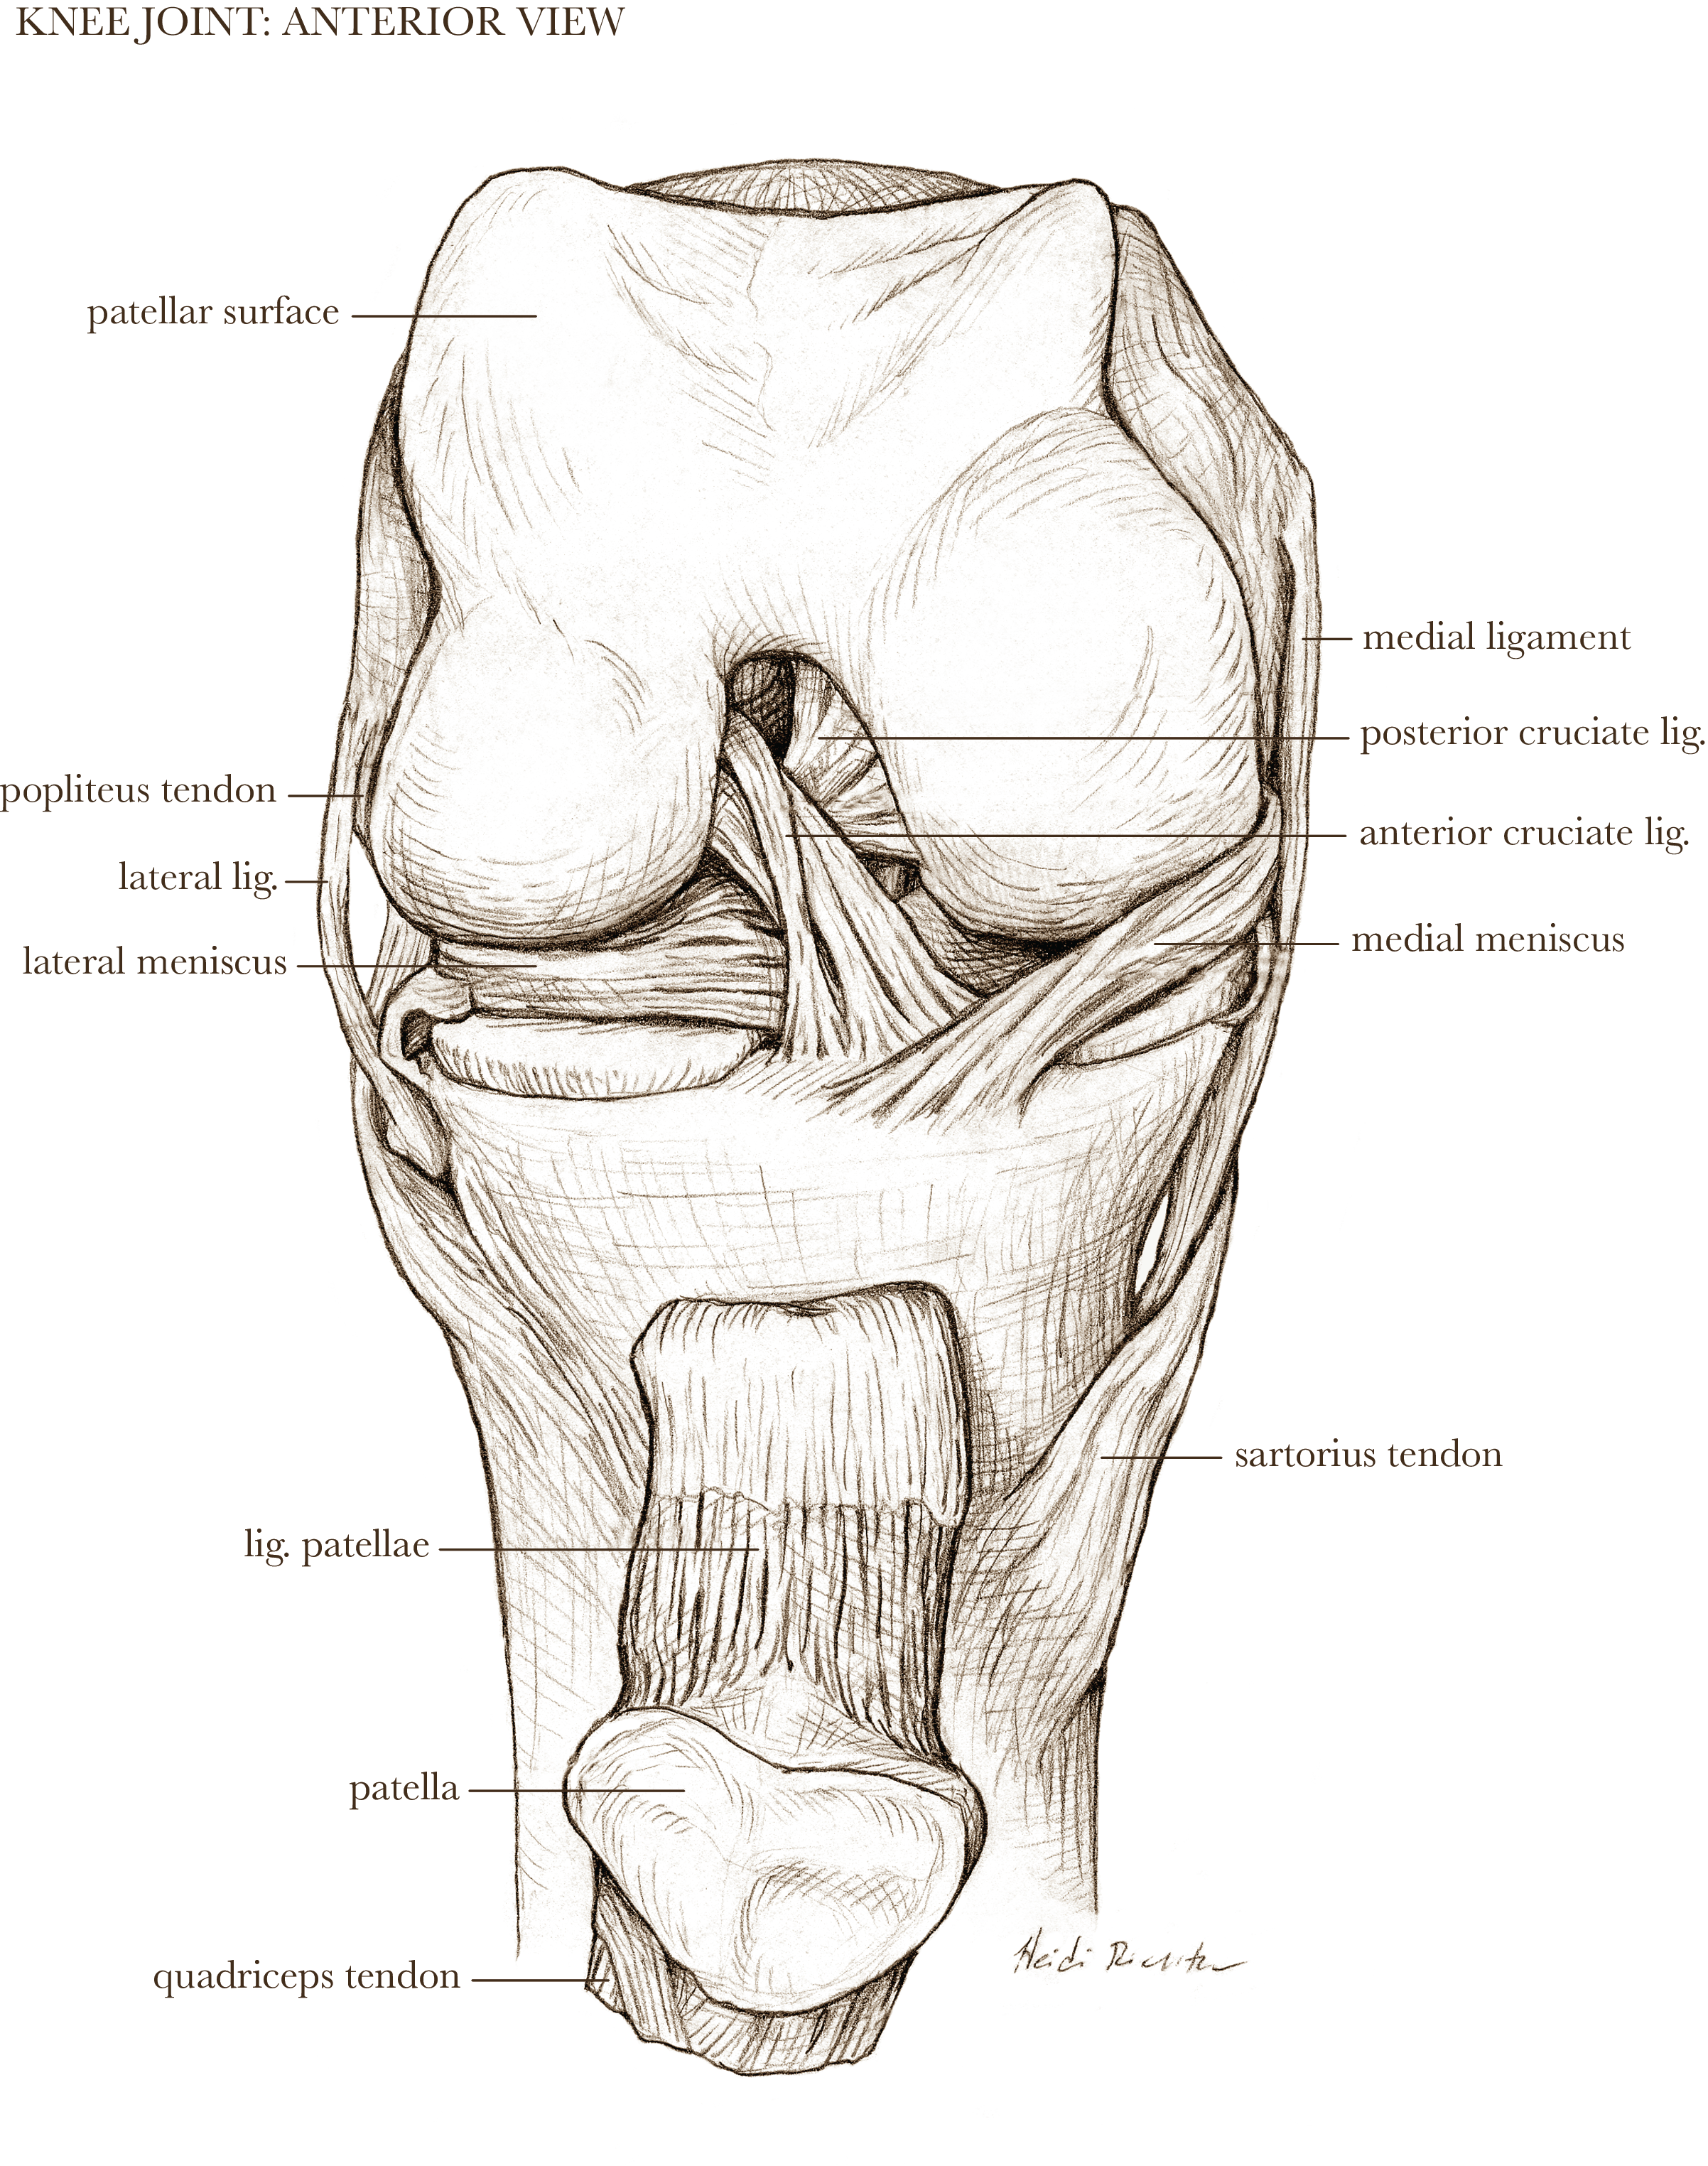

Textbook illustration

I have nearly twenty years of experience in text book publishing, having illustrated books from grade school to graduate level, and in subject areas from human anatomy to biology and geology. I never say no to projects involving dinosaurs.

Medical-legal illustration

I can create client-specific illustrations for your personal injury or malpractice cases to both inform the jury (who often don’t have experience with hospital images) as well as gain sympathy for the affected individual. I can work directly with medical experts to ensure accuracy and admissibility in court.

Patient education

Illustrations can help patients understand surgical procedures they or a loved one are planning to have, or explain how a medication works in the body.

Licensable work

Illustrations shown below are owned by the artist and available for non-exclusive licenses, contact me for more information.